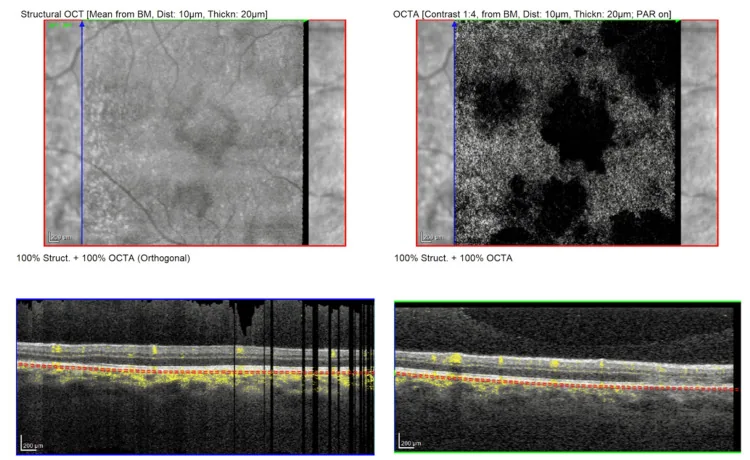

| OCT | 外網膜過反射、EZ消失 | EZ回復、RPE萎縮 |

| OCTA | 脈絡膜毛細血管血流欠損 | 部分的血流回復 |

OCT(光干渉断層計):活動期には外網状層からRPEにかけて広がる高反射像を認め、エリプソイドゾーン(EZ)の消失は中心窩波及と視力低下を示唆する。11)脈絡膜肥厚も認められる。5)GoldenbergのOCT分類では4段階(Stage 1: ドーム状隆起+EZ破壊、Stage 2: EZとRPEの分離、Stage 3: RPE過反射+EZ/RPE癒合、Stage 4: 消退期)に分類される。2)

OCTA(光干渉断層血管造影):脈絡膜毛細血管板の血流欠損を検出できる。11)治療経過とともに血管密度が回復する所見が報告されている。5)

現在最も支持されているのは、脈絡膜毛細血管板の輸入細動脈に発生した遅延型過敏反応(IV型アレルギー)による閉塞性血管炎説である。脈絡膜毛細血管板への一次的関与があり、RPEおよび外網膜の障害は二次的に生じると考えられている。11)OCTAでは外網膜変化が脈絡膜毛細血管板の血流欠損と共局在することが確認されており、この仮説を支持する。11)

OCTAは脈絡膜毛細血管板の血流欠損を非侵襲的に定量化でき、診断のゴールドスタンダードとなりつつある。5)治療経過における血管密度の変化(入院時→5週後)をモニタリングできる可能性がある。

Sarnaら(2025)は長期経過観察例でOCTAとFAFによる連続評価を行い、脈絡膜毛細血管板の血流密度回復と視機能改善の相関を報告した。5)